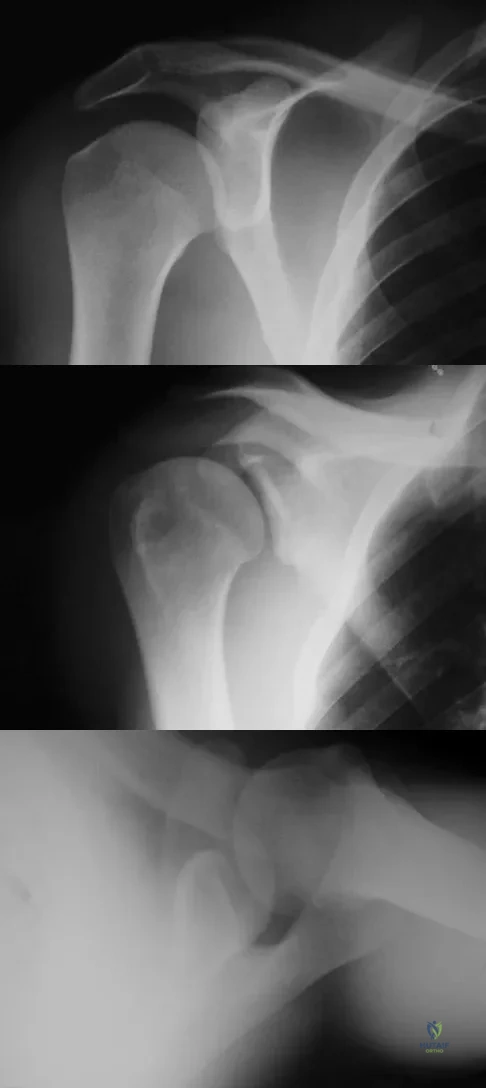

A 21-year-old right hand-dominant male collegiate swimmer reports painful clicking in the right shoulder. He states that he can occasionally feel his shoulder "slip out" when he is working out. AP, true AP, and axillary radiographs are shown in Figures 39a through 39c. What is the next most appropriate step in management?

Explanation